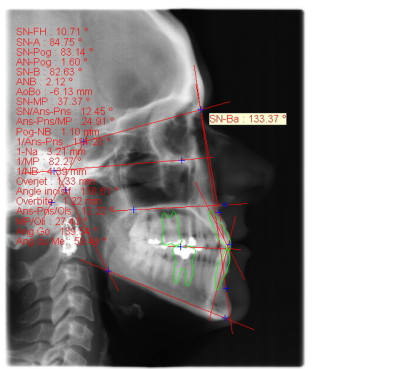

voici de la cas d'un jeune dame de 23 ans qui présente une full classe III subdivision Droite (associée à des compensations incisives de classe III), sur un terrain hyperdivergent. on note un encombrement inferieur d'environ 2 mm et une abrasion des bords triturants des incisives inf (Motif de la consultation)